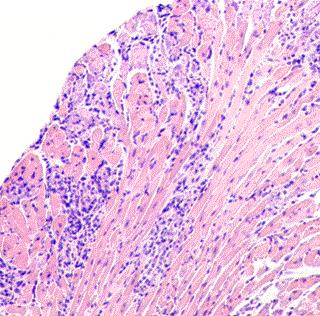

A review article has been published in the journal Current Pharmaceutical Design which provides an overview of therecent literature discussing the different clinical forms of heart disease resulting from virus infections including the prognosis, and current therapies. Many common viruses causing respiratory illness, including enteroviruses and influenza viruses among others, have the potential to infect the heart and initiate an immune response to the infection. These viruses can also produce mild to lethal cardiac injury.

Viral myocarditis is a leading cause of sudden unexpected death from cardiovascular causes primarily in men who are less than 40 years in age. Women either have a lower incidence of viral myocarditis or develop less severe infection than men. The infection can exist as an acute and self-limiting form (fulminant myocarditis) in which patients usually recover once the virus is cleared. However, patients with severely compromised cardiac function may require temporary use of a left ventricular assist device. Other patients develop chronic myocarditis, a progressive inflammation of the heart muscle, which results either from the establishment of persistent virus infections that the body cannot eliminate or the induction of autoimmunity to heart proteins. Chronic myocarditis lasting many months and years ultimately results in dilated cardiomyopathy which may require heart transplantation. It is estimated that up to 30% of allclinical dilated cardiomyopathy cases result from underlying viral infections.

Experimental animal models have been used to investigate many aspects of the clinical disease such as the sex bias in myocarditis where testosterones in males promote autoimmunity in the heart while estrogens in females suppress virus infection and autoimmunity. Knowledge from animal studies is now being applied to the clinical disease and this should lead to improved diagnosis and therapy.